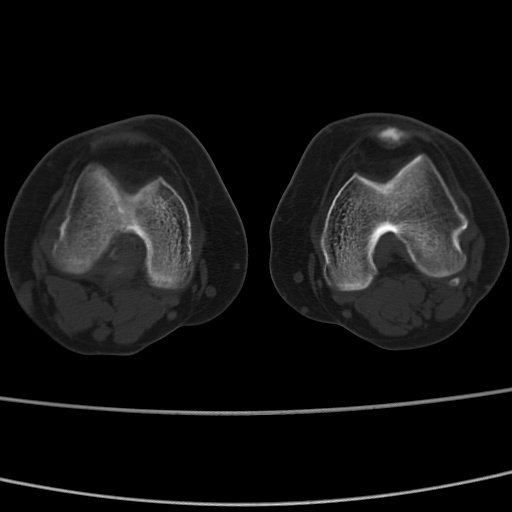

女性,50岁。【请提供患者临床症状体征】

右膝关节退行性改变,关节游离鼠。

右膝关节退行性改变,滑膜黏液囊钙/骨化并游离。

右膝关节退行性改变